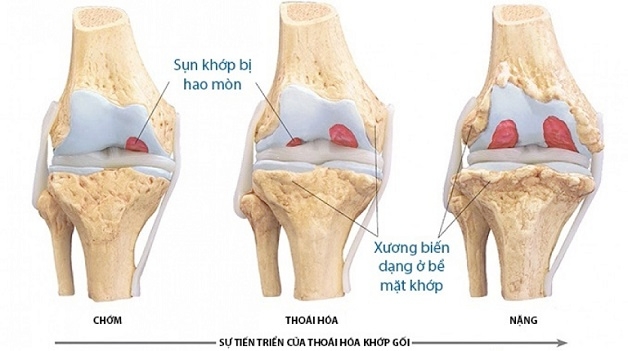

Chụp mri khớp gối có thể phát hiện, đánh giá quá trình thoái hóa khớp gối ở giai đoạn nào để có tư vấn phù hợp.

– Đối với thoái hóa khớp gối khi chụp MRI có thể đánh giá mức độ thoái hóa, từ đó bác sĩ sẽ đưa ra tư vấn phù hợp.